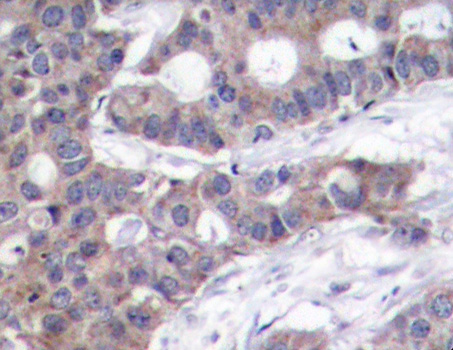

• AP0229: image 2

Immunohistochemical analysis of paraffin-embedded human breast carcinoma tissue using Phospho-STMN1-S16 antibody.